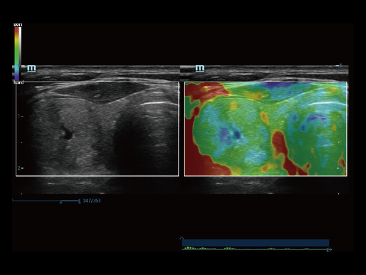

Sinds de oprichting van het bedrijf is Mindray voortdurend op zoek naar nieuwe manieren om het diagnostisch vertrouwen te vergroten. Resona 7 wordt aangestuurd door de meest revolutionaire ZONE Sonography?-technologie. Zijn nieuwe ZST+-tilt de kwaliteit van ultrasoundbeeldvorming naar een hoger niveau door middel van zoneacquisitie en kanaalgegevensverwerking.

Naast de hoogwaardige beeldvormingskwaliteit verbetert de Resona 7 tevens de klinische onderzoeksmogelijkheden met de revolutionaire V Flow voor vasculaire hemodynamische evaluatie, en de intelligentste vlakacquisitie van een 3D-gegevenssets voor de diagnose van het foetale, centrale zenuwstelsel. Met zijn combinatie van de meest intu?tieve, op vingerbewegingen gebaseerde multi-aanrakingsbediening en alle essenti?le klinische functies loopt de Resona 7 voorop in de nieuwe golven van ultrasoundinnovatie.